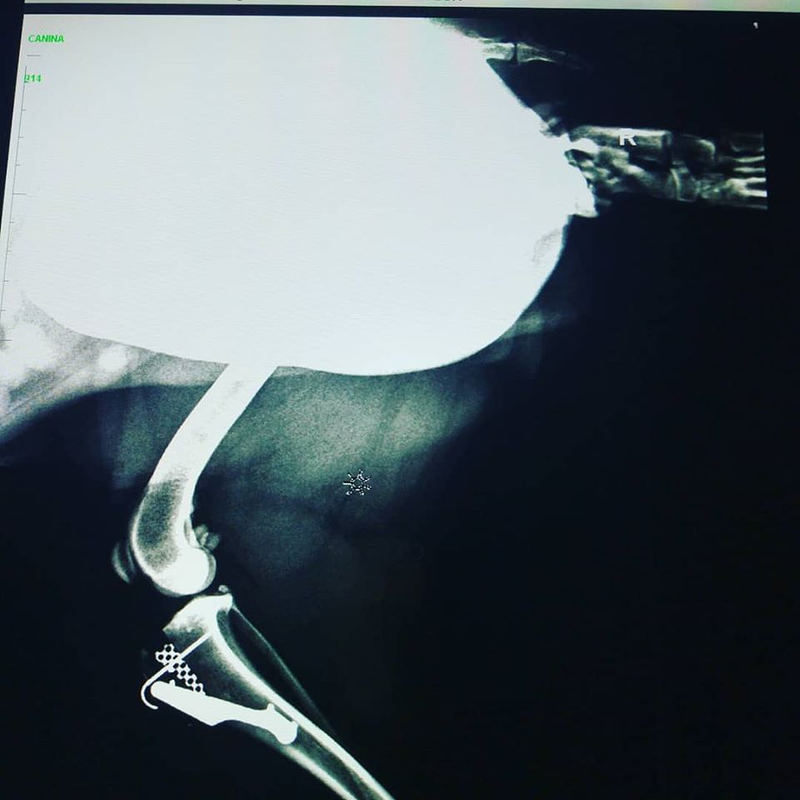

Tratamientos: Oftalmología, Laboratorio, Cirugía, Dermatología, Oncología, Nutrición

- Cirugia

- Ecografia

- Traumatologia

- Ortopedia